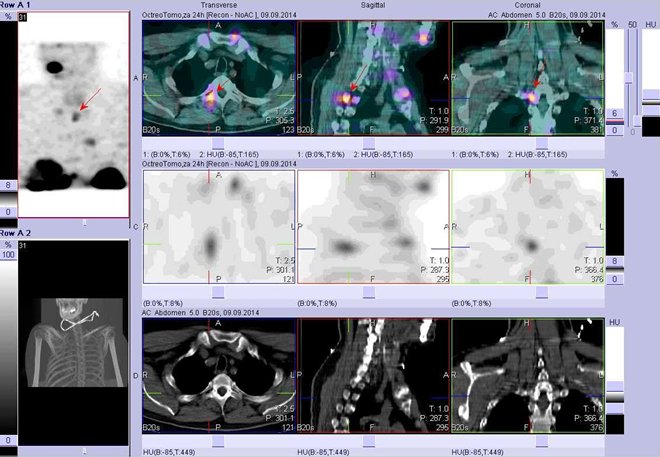

/ Obr. č. 8: Fúze obrazů SPECT a CT. Vyšetření 24 hod. po aplikaci radioindikátoru. Zaměřeno na ložisko v krční uzlině vpravo.

/

/ Obr. č. 9: Fúze obrazů SPECT a CT. Vyšetření 24 hod. po aplikaci radioindikátoru. Zaměřeno na ložisko v krční uzlině vpravo.

Je patrná fyziologická depozice radioaktivity v obou ledvinách, slezině, střevě, močovém měchýři. Dále pozorujeme mnohočetná patologická ložiska zvýšené depozice radioaktivity v obou jaterních lalocích, skeletu (hrudní obratle, sternum, sternoklavikulární skloubení, žebro, nejméně dvě ložiska v pánvi), v krční uzlině.

Nález při vyšetření Octreoscanem svědčí pro mnohočetná ložiska se zvýšenou hustotou somatostatinových receptorů – metastázy – v popsaných lokalizacích.